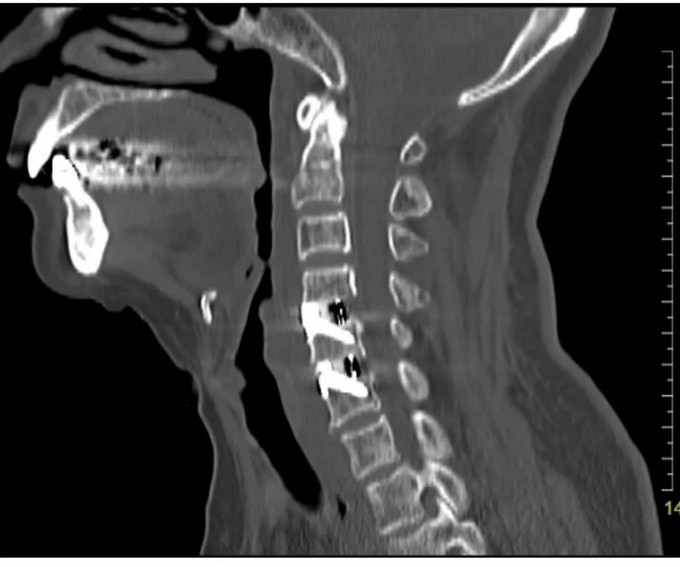

术前影像

颈椎CT矢状位

颈椎CT横断位 可以看到明显突出的骨赘